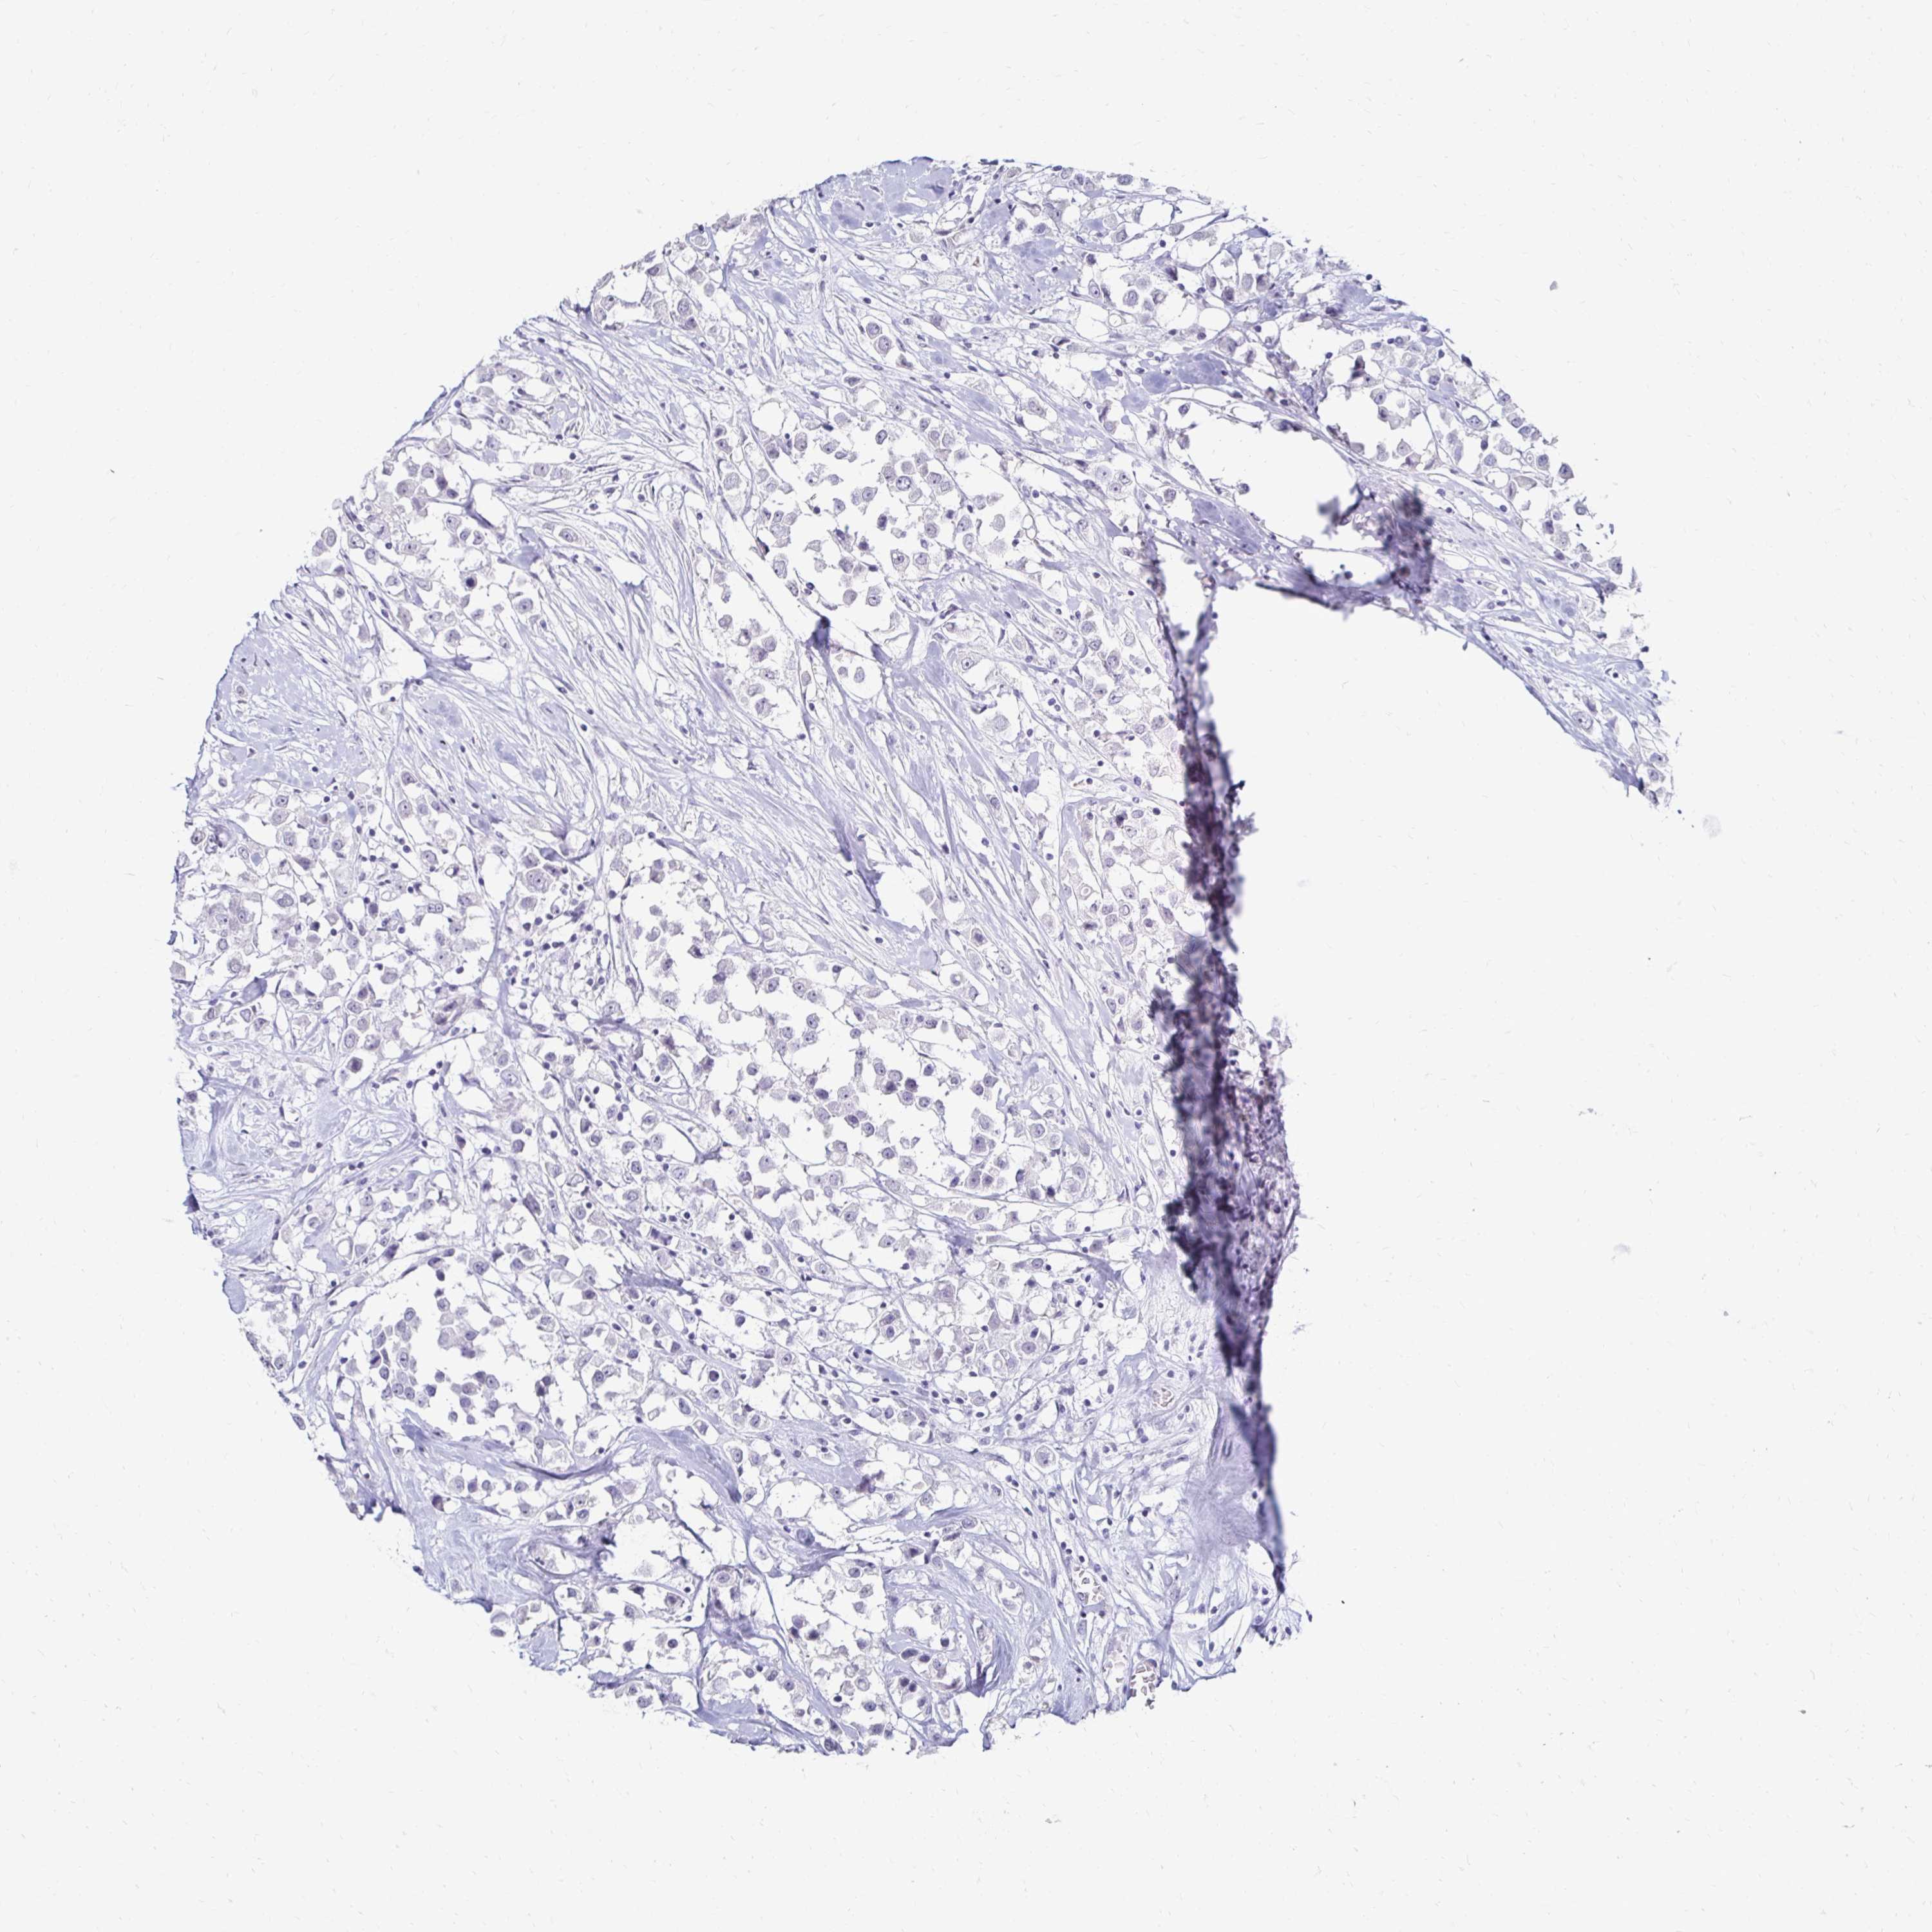

CANCER BREAST CANCER Show tissue menu

BRCA TCGA BRCA VALIDATION PROTEIN EXPRESSION